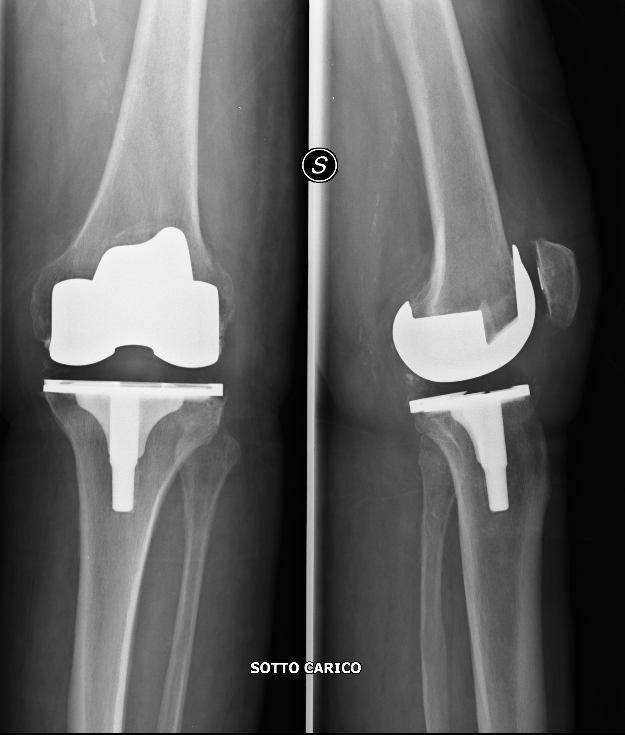

L’intervento consiste nel sostituire l’articolazione artrosica (malata) con una artificiale, creando nuove superfici di contatto e scivolamento tra le ossa del femore e della gamba.

L’intervento è eseguito in anestesia locoregionale o generale; il tipo di anestesia più indicato al Suo caso, tuttavia, sarà scelto dall’anestesista che Le fornirà tutte le informazioni utili in merito. L'intervento richiede di un laccio applicato alla coscia per evitare sanguinamenti eccessivi e di un’incisione sulla parte anteriore del ginocchio con esposizione dell’articolazione. Con appositi strumenti viene tagliata e preparata la superficie del femore e della tibia e quando necessario anche della rotula, asportando le superfici articolari danneggiate. Esse vengono ricoperte con elementi in metallo (cromo-cobalto e/o titanio e/o metallo ceramizzato) che si articolano tra di loro tramite un inserto (posizionato tra le superfici metalliche) in materiale plastico, chiamato polietilene. In genere le componenti metalliche vengono fissate all’osso con resine a presa rapida (cemento). Alcuni tipi di impianto possono essere applicati all’osso senza cemento (raramente). Segue la ricostruzione dei piani anatomici e la sutura di sottocute e cute. Può essere necessario il posizionamento di un drenaggio. Dopo l’intervento potrebbe essere necessario eseguire delle trasfusioni di sangue.